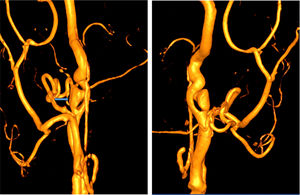

La analítica básica de urgencias no mostró alteraciones. El electrocardiograma y la radiografía de tórax fueron anodinas. Se solicitó TC craneal sin lesiones y se amplió el estudio mediante angiografía-TC que puso de manifiesto: en la arteria carótida interna (ACI) izquierda se visualiza en su origen una imagen de flap intimal, con posterior disminución progresiva e irregular de su luz («signo de la cuerda») hasta su segmento petroso. En el segmento cervical de la ACI derecha se visualiza un flap intimal focal con imagen de seudoaneurisma adyacente (fig. 1).